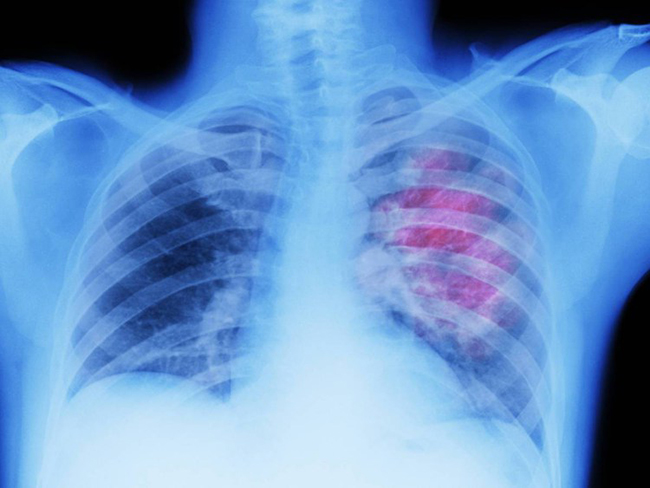

უკვე 72 საათის გასვლის შემდეგ ფილტვებში აღდგება წამწამისებრი ეპითელიუმი, რომელიც სასუნთქ გზებს წმენდს.

არტერიული წნევა ჩადგება ნორმაში, ეს კი იმას ნიშნავს, რომ ინსულტისა და გულ-სისხლძარღვთა დაავადებების გაჩენის რისკი საგრძნობლად შემცირდება.

2 კვირაში შეგიჩერდება ხველა. ის მაშინვე არ გაივლის, რადგან შენს ფილტვებს დრო სჭირდება აღსადგენად და დაგროვილი მავნე ნივთიერებების გამოსადევნად. ასევე მთლიანად აღგიდგება სისხლის მიმოქცევა, რაც გავლენას მოახდენს შენს სქესობრივ ცხოვრებაზე.